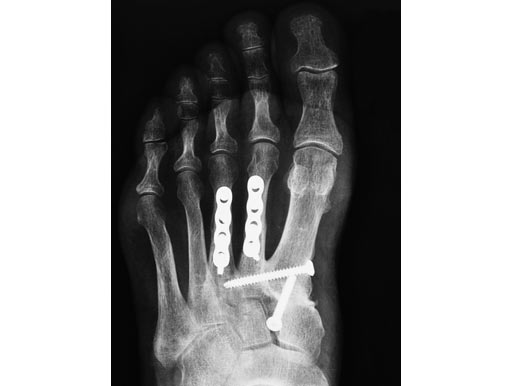

LC-DCP Adaption Plate for metatarsal osteotomy

The LC-DCP Adaption Plate 2.4 with four holes is an addition to the existing implants and instruments of the Modular Foot Set 2.4.

The LC-DCP Adaption Plate 2.4 is indicated for treatment of fractures and osteotomies on the 2.4. metatarsal bone. The need for compression and the possibility of movement of the plate is very important for these procedures, therefore the DC-hole is more advantageous compared to the LCP. The standard DCU hole allows for 1480 of angulation and enables compression on both directions.

Furthermore, the plate has a scalloped contour providing a better view to the bone.

Plate in situ after corrective osteotomy and arthrodeses

Case provided by Kaj Klaue, Switzerland.